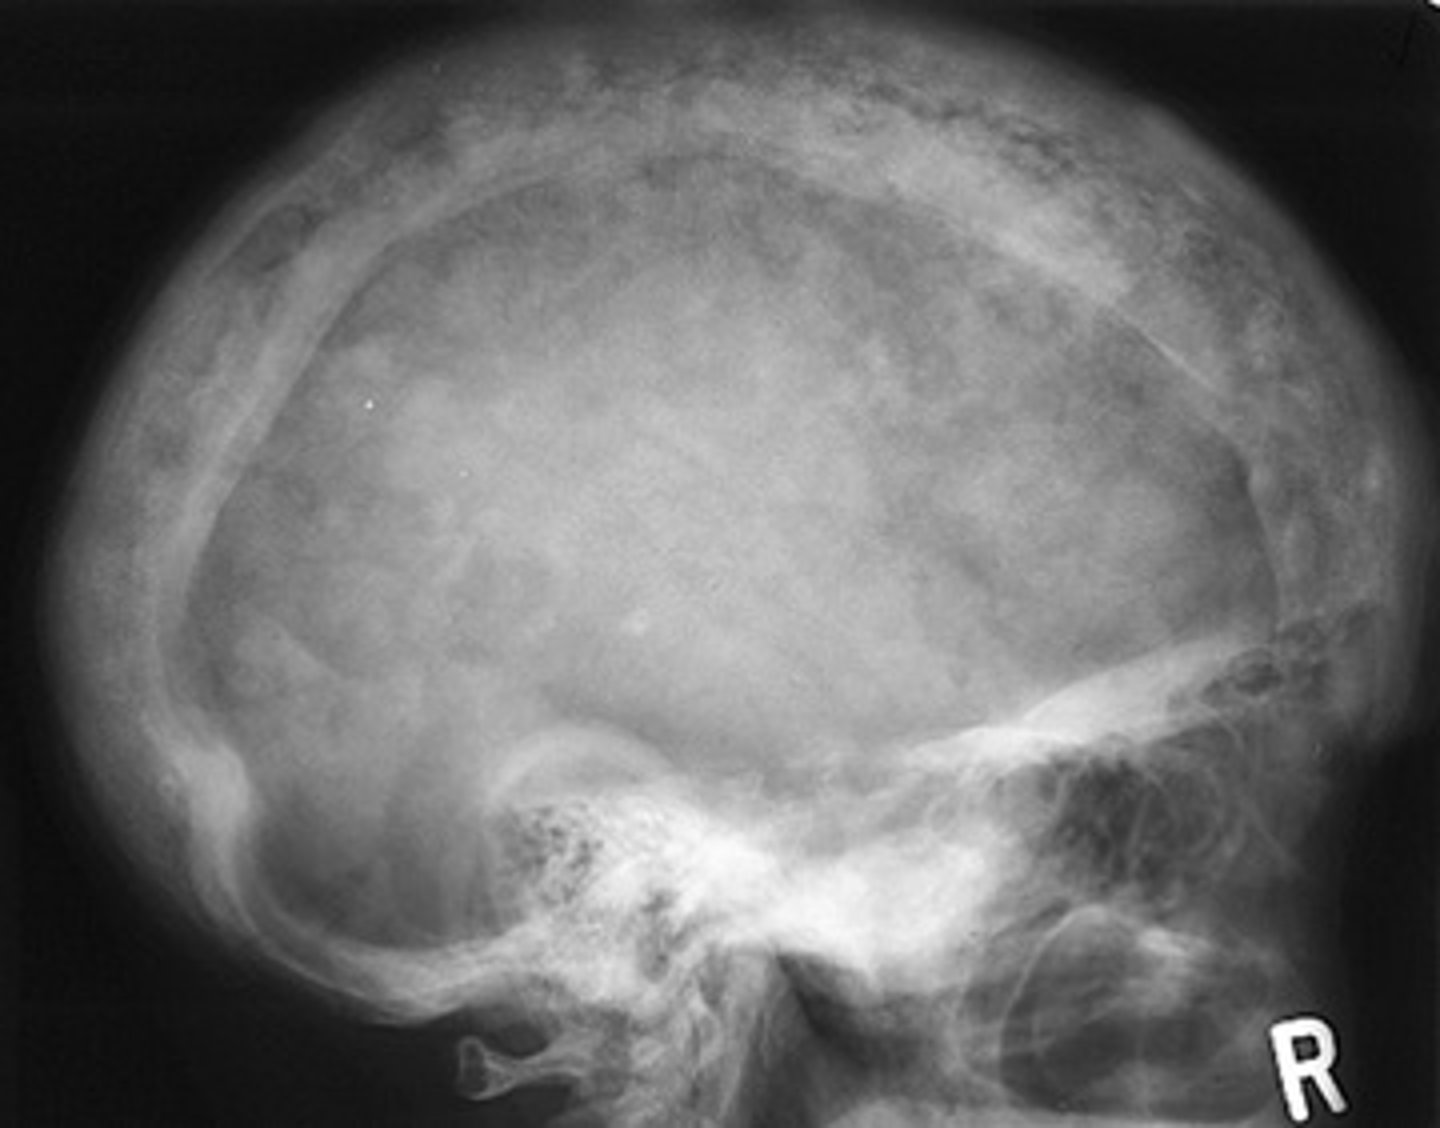

Sickle cell anemia

The radiographs show widening o the diploic space (between the inner and outer cortices) and a "hair-on-end" appearance are features of what pathology?